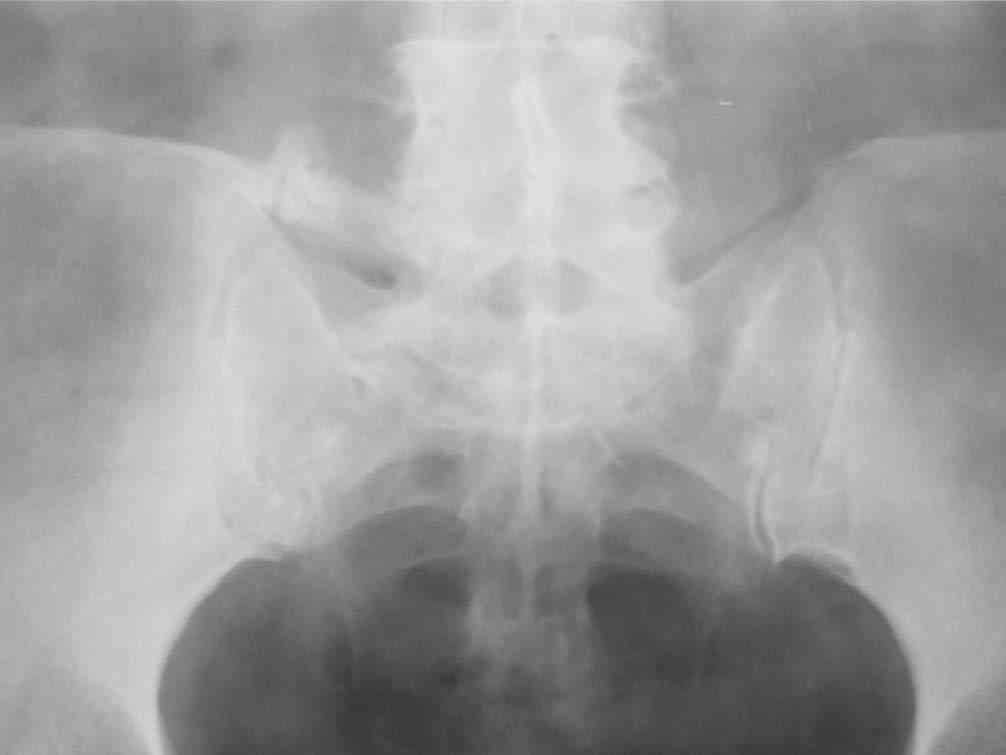

[Ortho] Одностороняя сакрализация 5 поясничного позвонка

Уважаемый Юрий Алексеевич! Спасибо огромное за подробное письмо, Ваш

опыт бесценен, обязательно воспользуюсь. Отправляю рентгенограмму

пациентки.